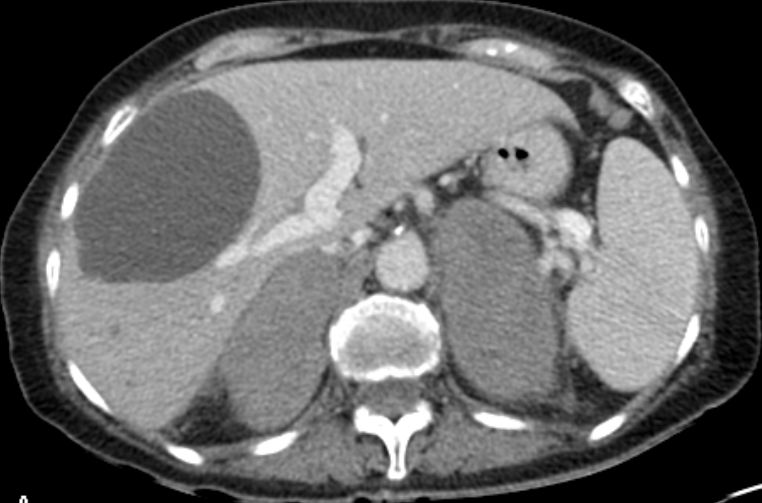

B-Zell-NHL der Nebennieren |

76-jährige Frau mit Inappetenz, rezidivierendem

Fieber, Hyponatriämie und Nebennierenschwellung. Hochmalignes B-Zellymphom. NB.

Leberzysten.